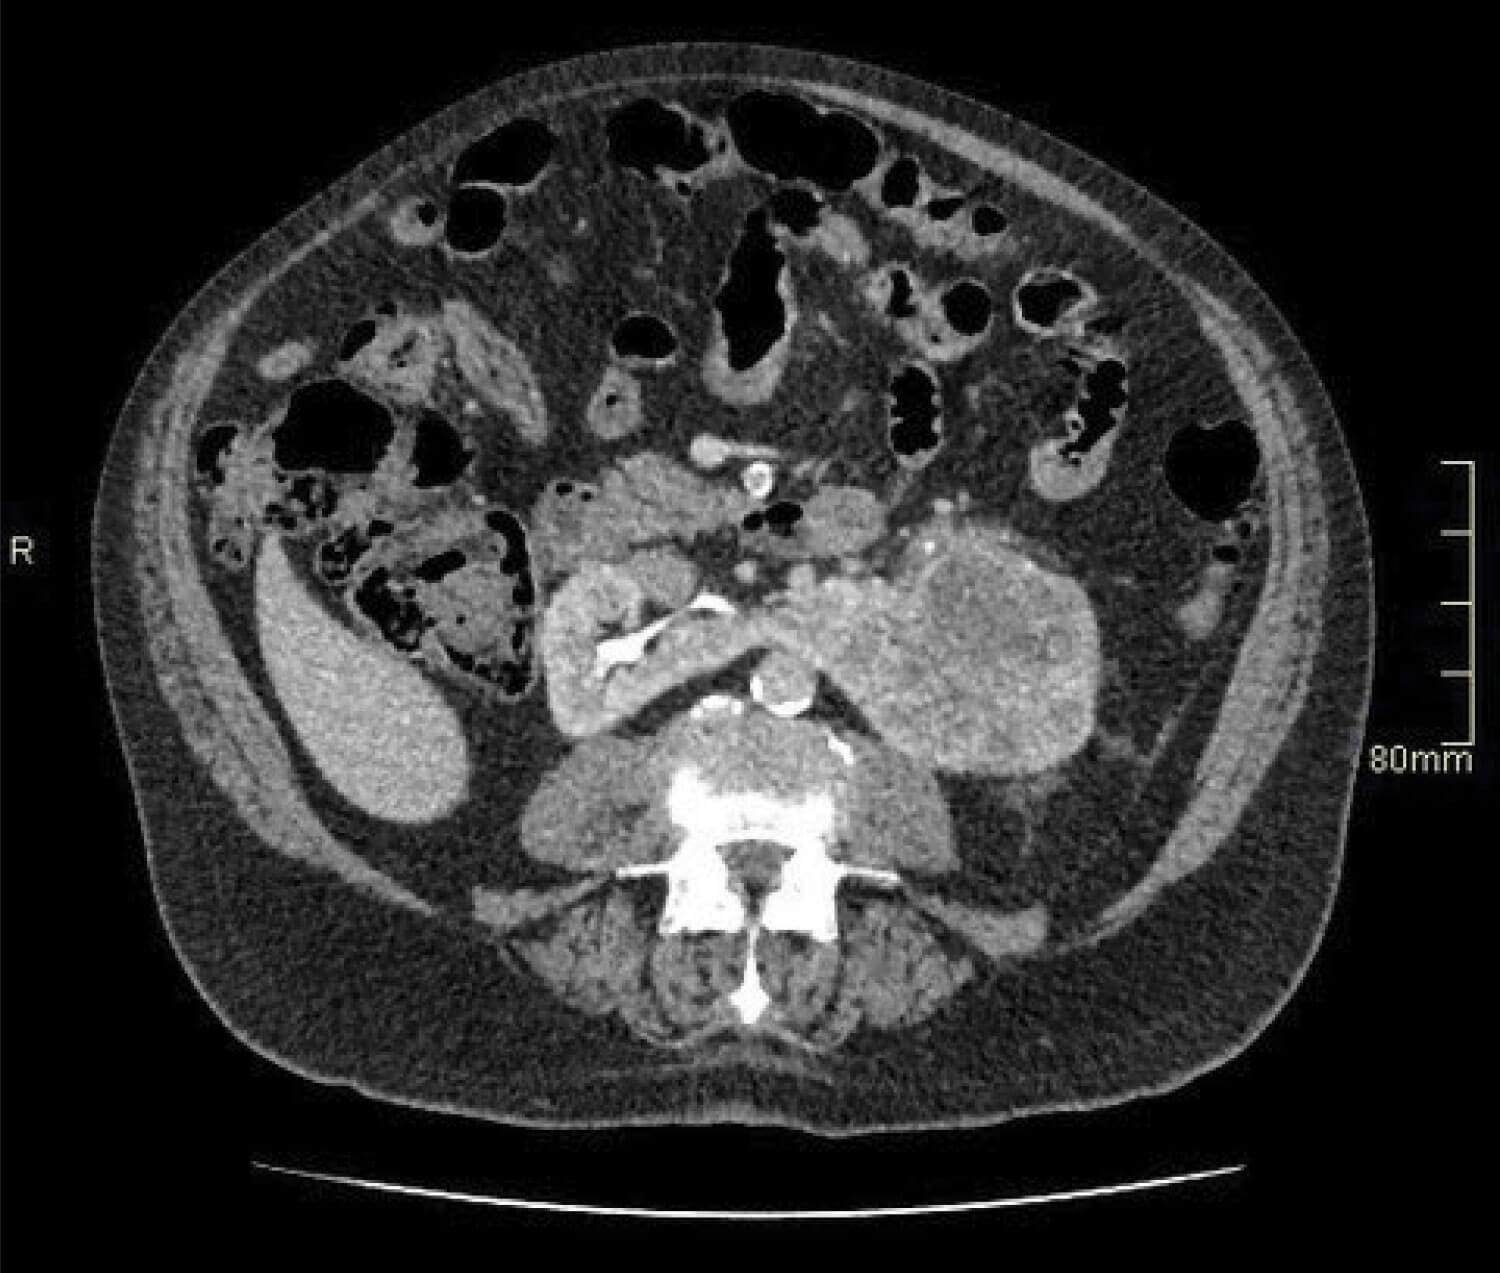

Figure 2.

- An 82-year-old man presents with visible haematuria. Flexible cystoscopy is normal, but what does the contrast CT image in Figure 2 show?

- The image shows an 8cm tumour in the left moiety of a horseshoe kidney.

- This tumour is T2a at least given the size visible here: further images would reveal invasion of the renal vein, T3a.

- A heminephrectomy is the definitive surgical management for a tumour of this size in a horseshoe kidney.6. T3a, Nx, Mx, and Leibovich score 8 (high risk) [7].